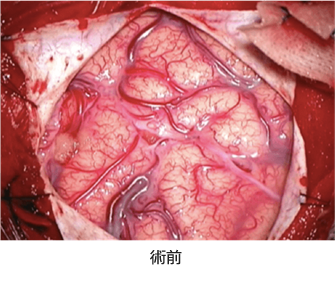

もやもや病の手術方法は、歴史的な変遷を繰り返して様々な手技が個々の施設で行われています。根本的な考え方は、手足の麻痺につながる中大脳動脈領域の血流動態改善が第一目的で、小児ではさらに前頭葉の血流動態改善という目的が加わります。頭皮内を走行している浅側頭動脈を頭蓋内の脳表血管に吻合する直接血行再建術(バイパス手術)と、血管が豊富な側頭筋や硬膜、帽状腱膜などを脳表に移動する間接血行再建術があります。間接血行再建術は、脳表に移動された組織から血管新生がおこり、血液が頭蓋外から脳に流入するという、この疾患特有の現象を利用した方法です。両者の違いは、直接バイパス手術では血流改善効果が吻合直後から得られるのに対して、間接的手術では血管新生までに3週間から1ヶ月という時間的な差です。従って、新生血管形成能が小児ほど確実でないと推測されている成人や、小児でも重症例で血流増加を急ぐ場合には直接バイパス手術が必要です。前頭葉に対して、浅側頭動脈の前頭枝を用いて2つ目の直接血管吻合を行う方法もありますが、知能予後の考慮という目的からは、血流改善に即効性は求めないと考えて、当科では前頭葉に対しては間接的手術を行い、手術時間を短縮して手術侵襲を低くしています。